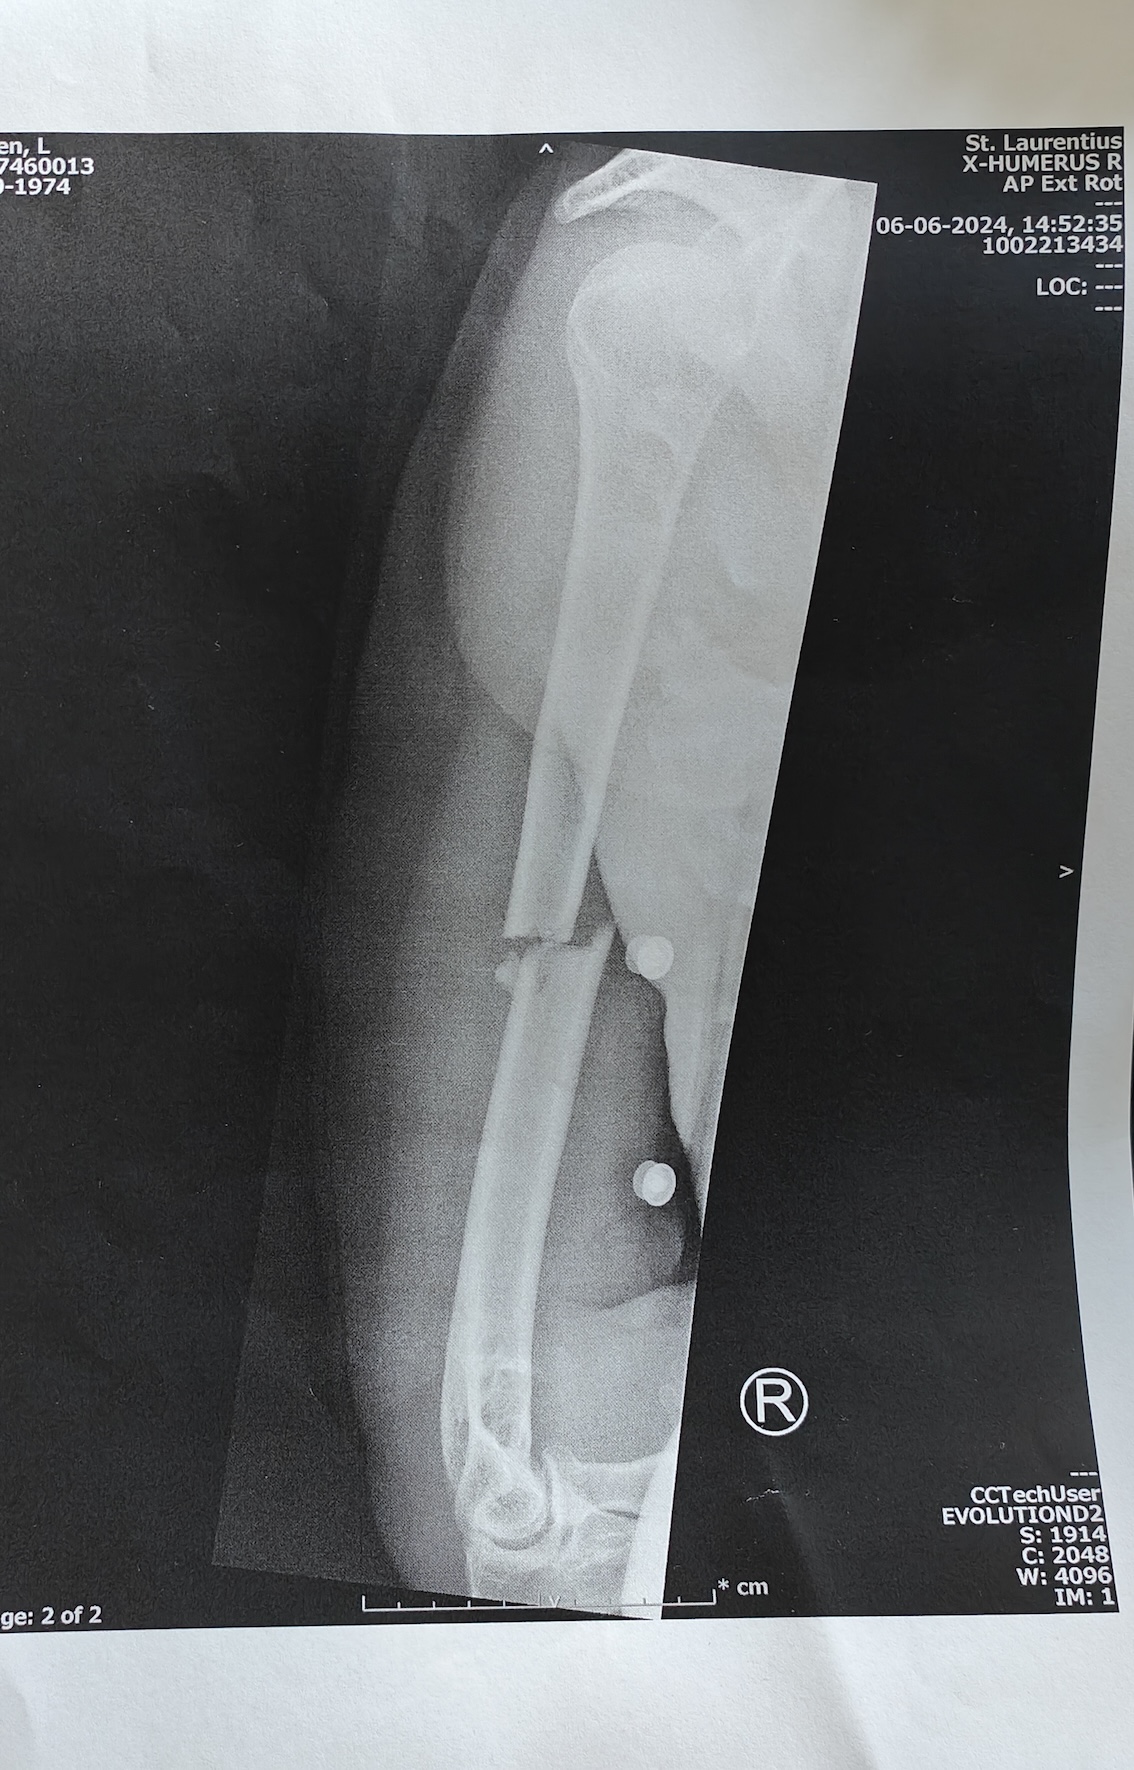

De val

Op de camping zie ik een vrouw met haar voet in het gips. Ze kijkt bedrukt als ze met haar krukken…